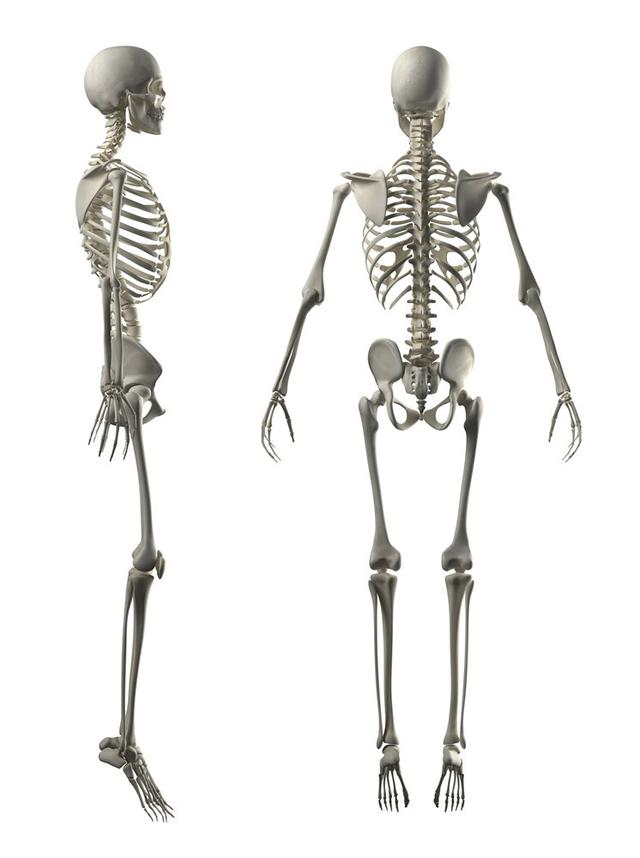

从一方面来说,人类是弱小的,容易生病,容易受伤,但从另一方面来说,人类也是强大的...